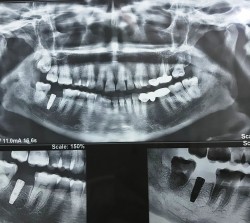

Our Dental Clinic is dedicated to providing the most up to date general dentistry, Oral & Maxillofacial Surgery, Orthodontic, Cosmetic Surgery, Dental Implants and family dentistry. Working As Assistant Professor in Oral & Maxillofacial Surgery Department in the University Medical & Dental College Faisalabad

Our Clinic has grown to provide a world class facility for the treatment of facility of facial fractures, Orthognathic Surgery, Odantogenic Infection, Odantogenic Cyst & Tumour, Oral Cancer, Laser Filling, Facial Swelling, Facial Pain, Wisdom Tooth Surgery, tooth loss, dental cosmetics and advanced restorative dentistry.

We are among the most qualified Oral & Maxillofacial Surgeon. We are among the qualified implant and Facial Surgery Treatment Provider in Faisalabad over 10 years of quality training and experience.

With over 10 years of dental experience and experience with Maxillofacial Surgery and Dental implants, we are experts in all facets of Maxillofacial Surgery and General dentistry.